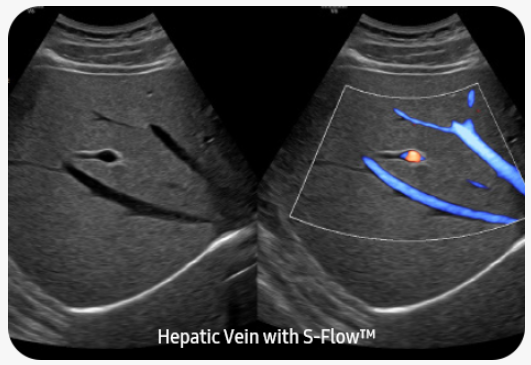

Vyšetření periferních cév |

S-Flow™směrová technologie, která pomáhá detekovat periferní cévy. Umožňuje přesnou diagnózu v případech, kdy je vyšetření krevního průtoku velmi obtížné.